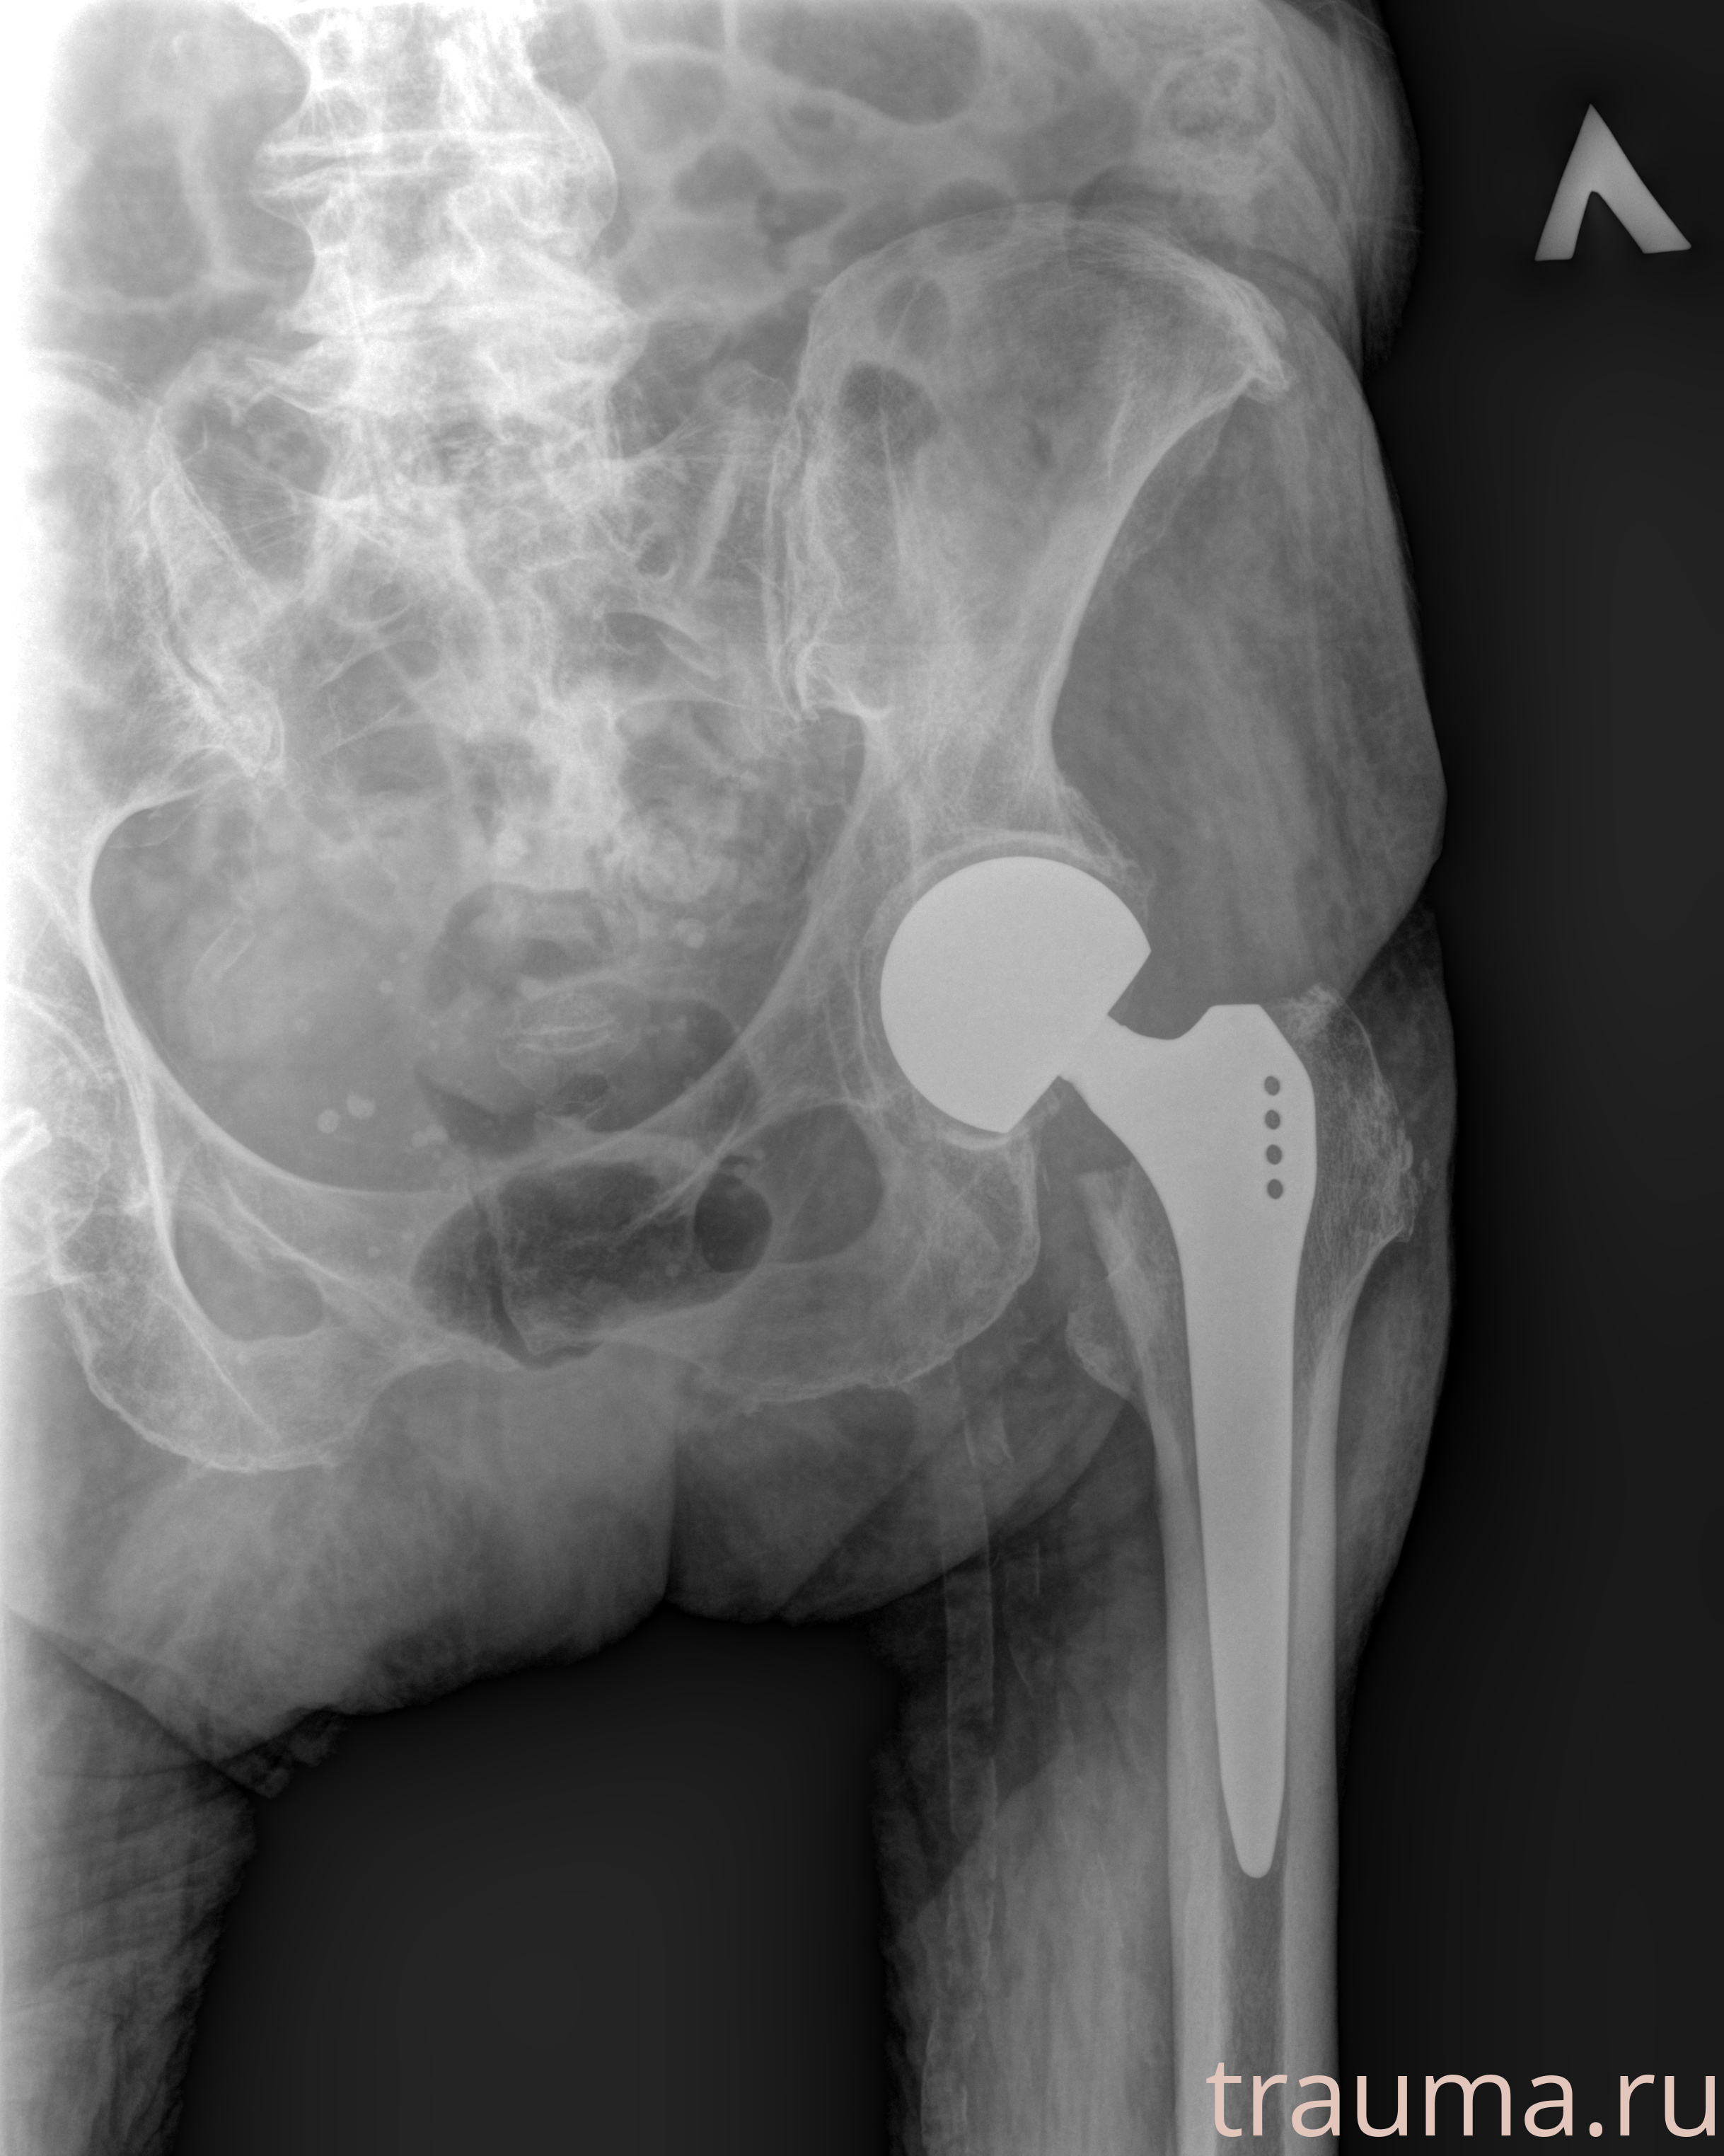

Первая помощь при переломе шейки бедра

Рентген на дому: по вашему адресу приезжает врач-рентгенолог, травматолог-ортопед с мобильным рентгеновским аппаратом, проводит диагностику травмы или заболевания, делает необходимые рентгенограммы, дает рекомендации по дальнейшему лечению. Получить качественные снимки в домашних условиях возможно благодаря уникальной методике, разработанной МосРентген Центром для института  Склифосовского